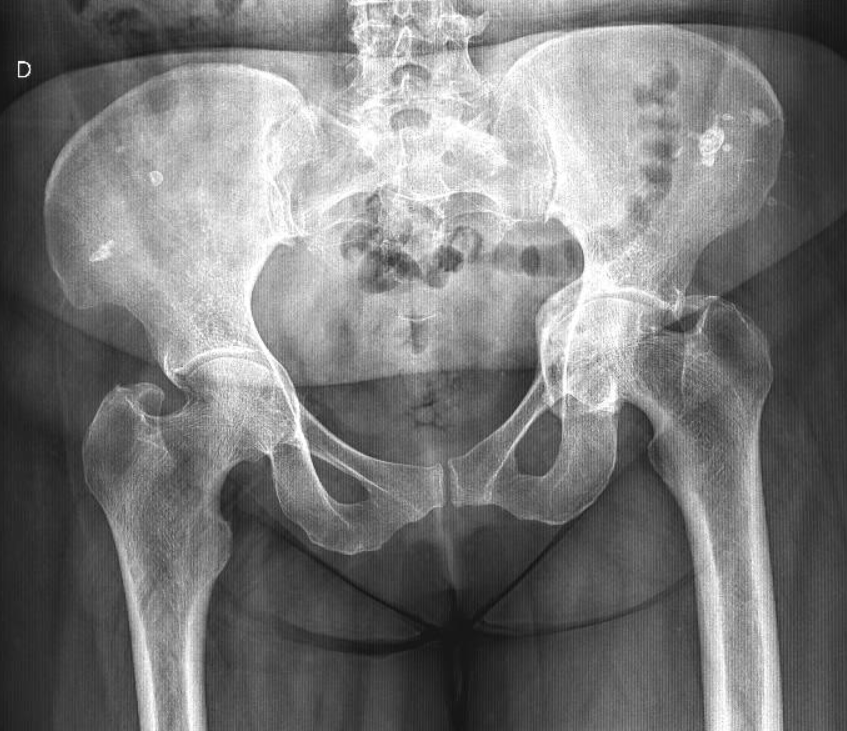

9/10/2025. 🟥🦴 What do you see here? (AP pelvis X-ray) Notice the altered trabecular pattern in the right femoral head — with a subtle articular collapse and a well-defined subchondral lytic lesion with sclerotic margins. Any guesses? 👀 #Radiology #MedTwitter